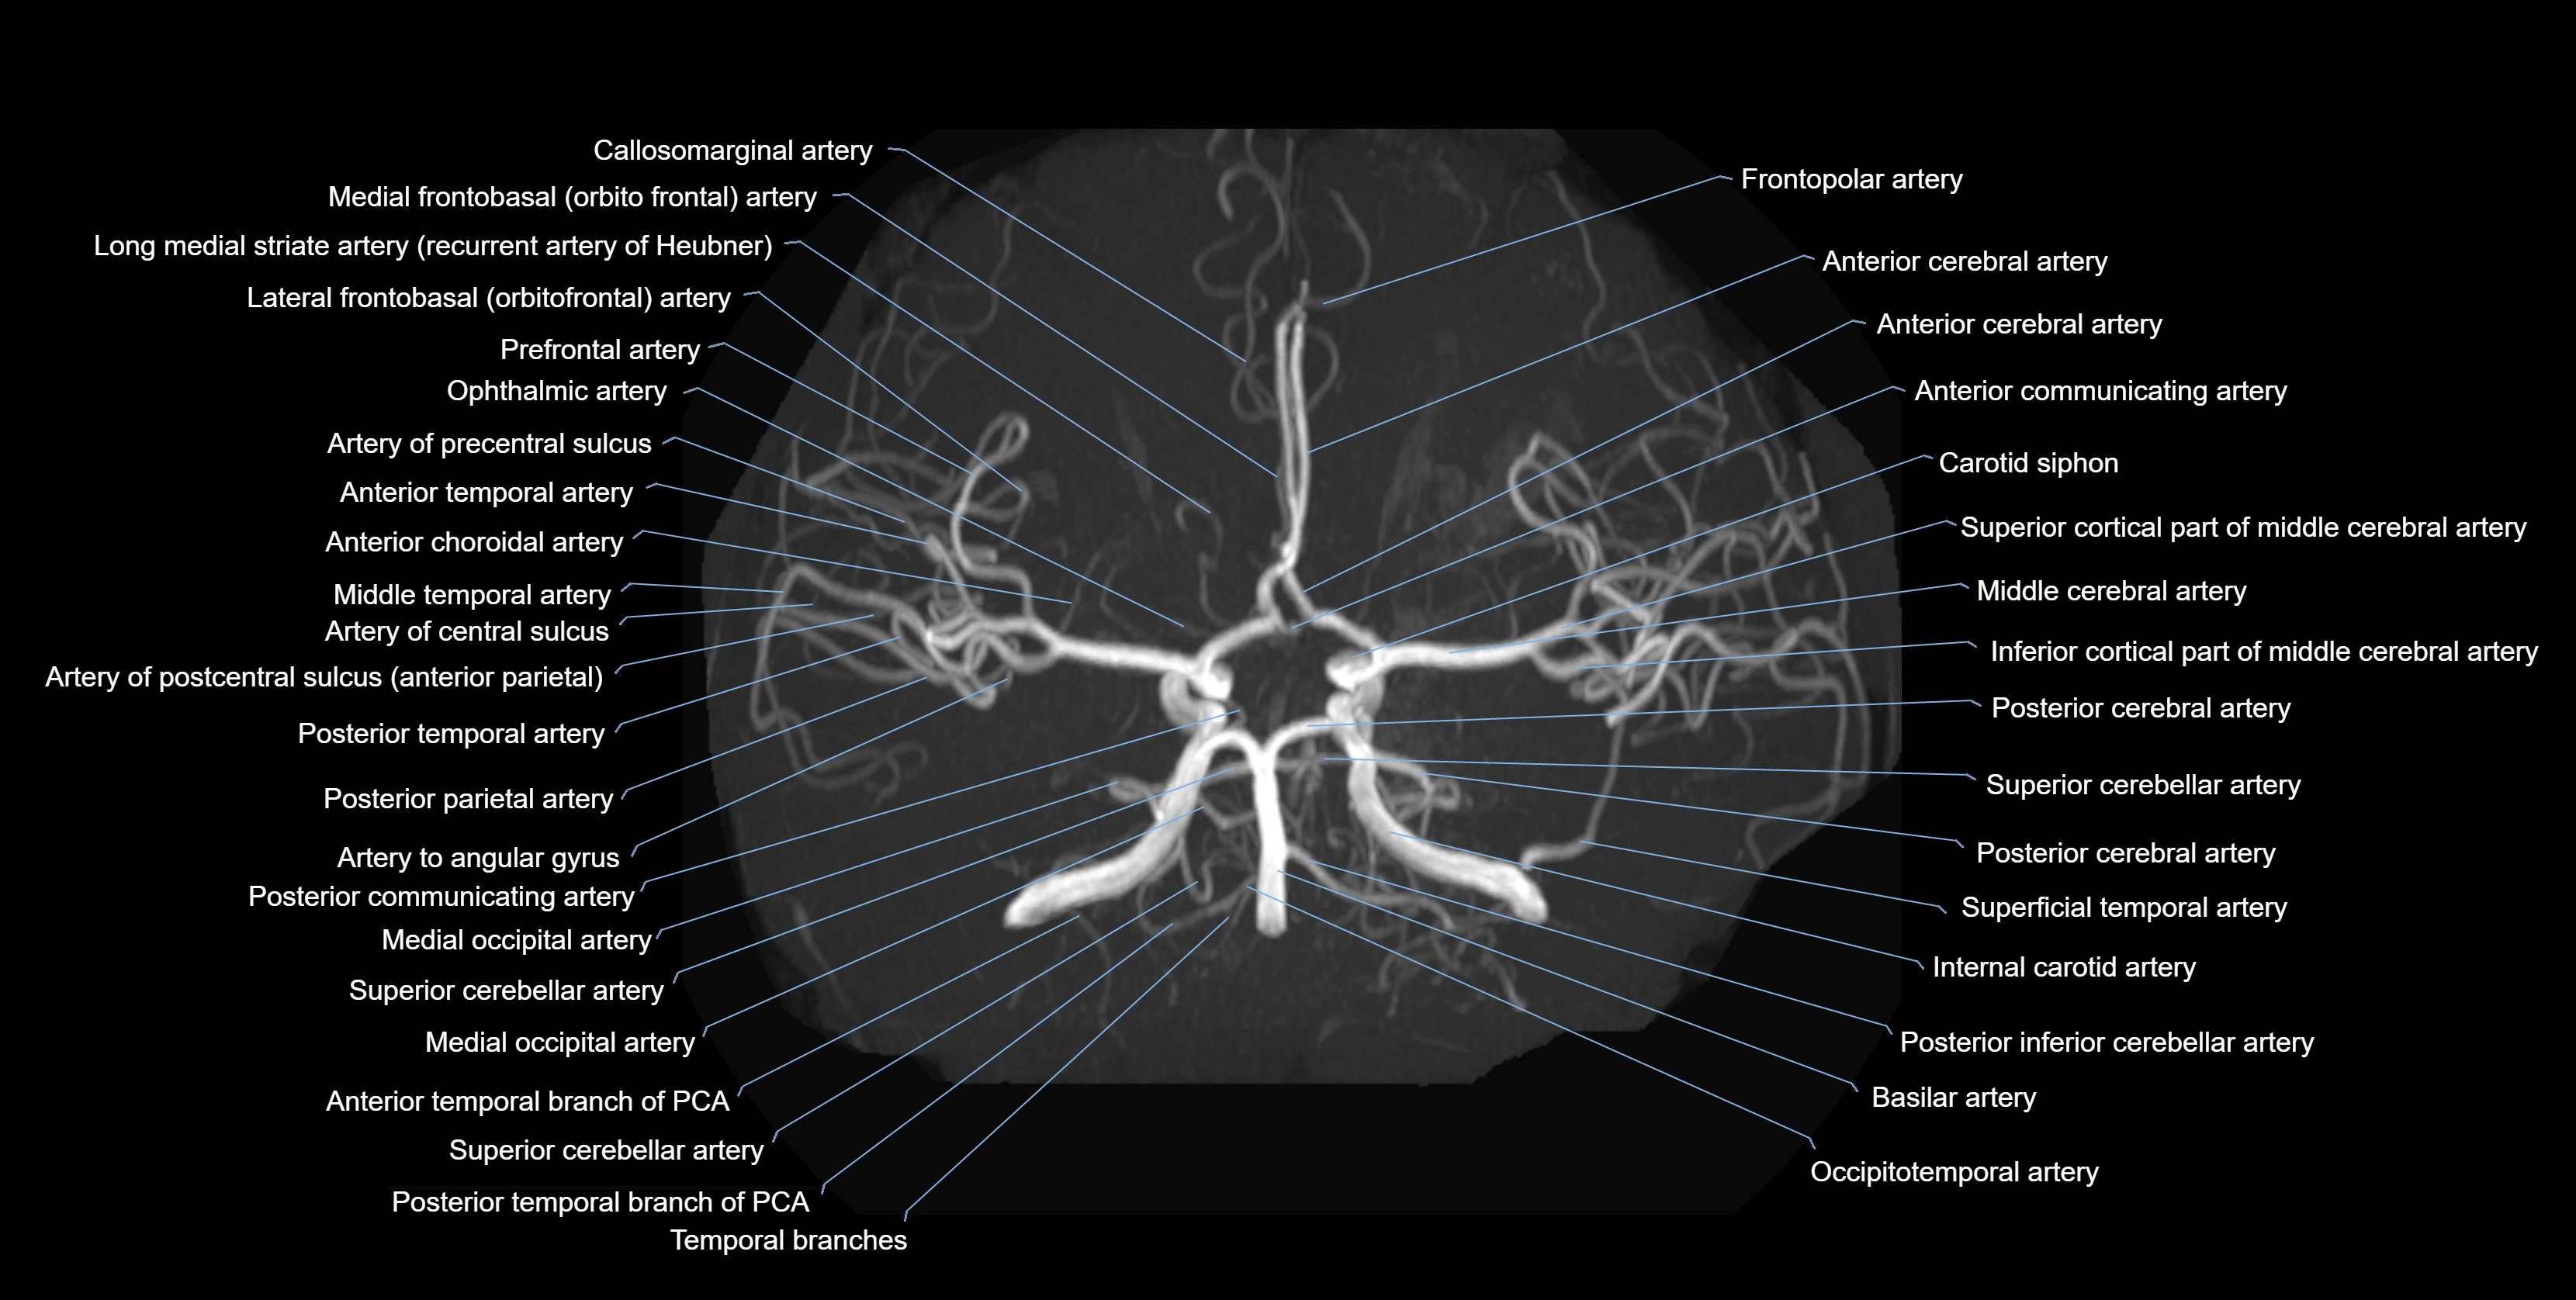

MRA (Magnetic Resonance Angiography):

• Flow-related enhancement makes the AChA appear as a bright, linear vascular signal against suppressed background

• High sensitivity for origin and proximal course; distal branches may be too small to resolve

• Detects stenosis, occlusion, aneurysm, AVM feeders

CTA (CT Angiography):

• Opacified with iodinated contrast, AChA appears as a bright high-attenuation vessel

• Visualized from ICA origin along optic tract toward choroid plexus

• 3D reconstructions depict its course and relation to adjacent arteries

• Gold standard for identifying aneurysms, occlusion, or vascular anomalies